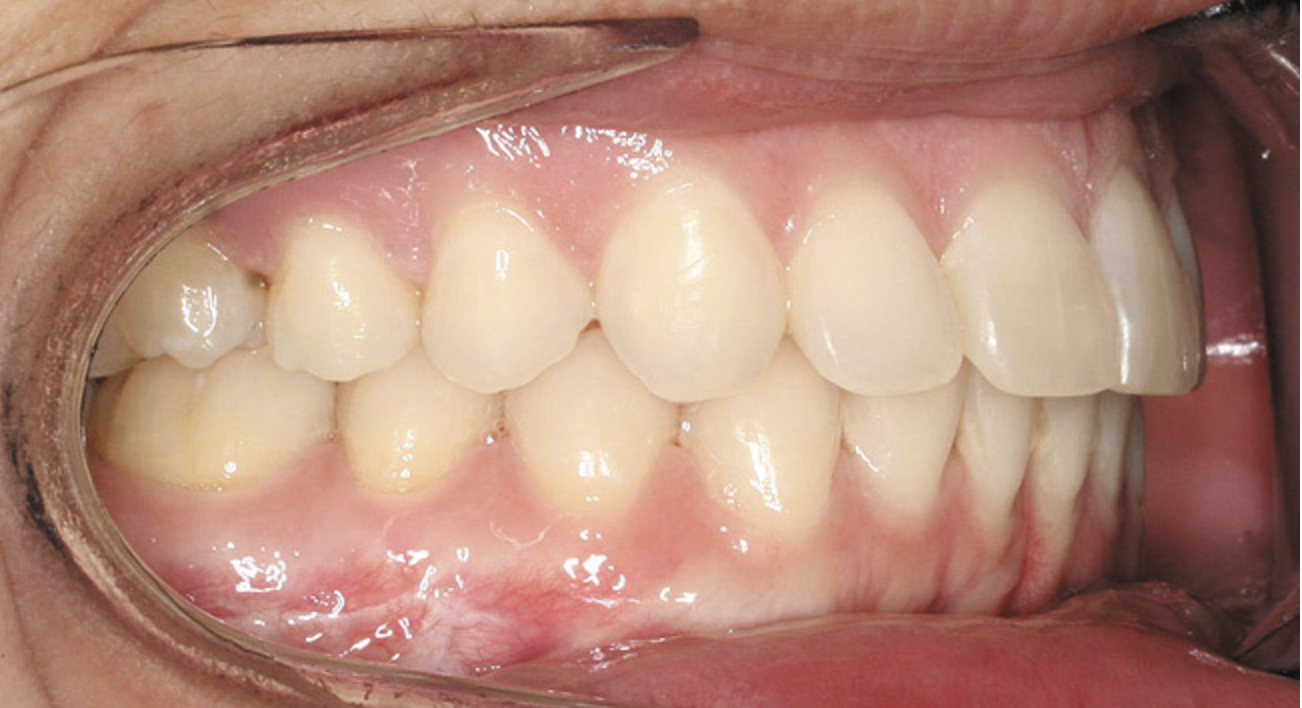

A stable TMJ is critical in establishing a normal functional occlusion. Unless the condyles are in a stable musculoskeletal position, there are always interferences to normal function and stress placed on the masticatory system.1-3,15 In orthodontics, the Angle classification of malocclusion using handheld models has been the standard to evaluate the fit of the teeth. However, it is not possible to truly identify the occlusion/malocclusion using handheld models. Before the occlusion can be evaluated, the clinician must ascertain the joint position and condition (Figure 7 and Figure 8).1,16

Figure 7A  This case is an example of the importance of evaluating the bite with the joints seated in a stable position. Orthodontic treatment was rendered to correct a

Figure 7A

Figure 7B  This case is an example of the importance of evaluating the bite with the joints seated in a stable position. Orthodontic treatment was rendered to correct a

Figure 7B

Figure 7C This case is an example of the importance of evaluating the bite with the joints seated in a stable position. Orthodontic treatment was rendered to correct a

Figure 7C

Figure 7D  This case is an example of the importance of evaluating the bite with the joints seated in a stable position. Orthodontic treatment was rendered to correct a

Figure 7D

Figure 8  Intraoral view of the occlusion of patient from Figure 7 after retreatment. The occlusion is adequate to finish with equilibration.

Figure 8